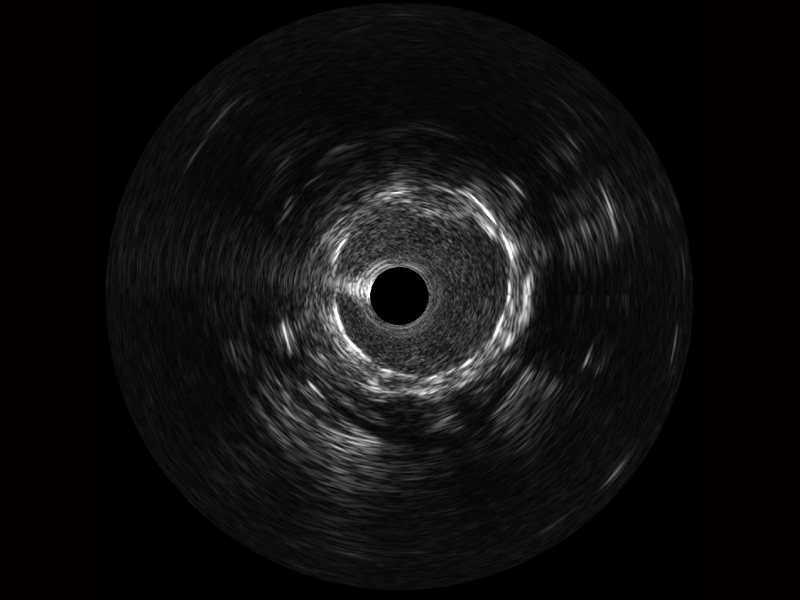

• 传统IVUS图像

对比传统IVUS导管成像,MILE米乐集团官网宽频IVUS图像的近场支架梁显影更细腻,远场中膜外血管仍清晰可辨,兼顾远中近,兼顾分辨力与穿透深度